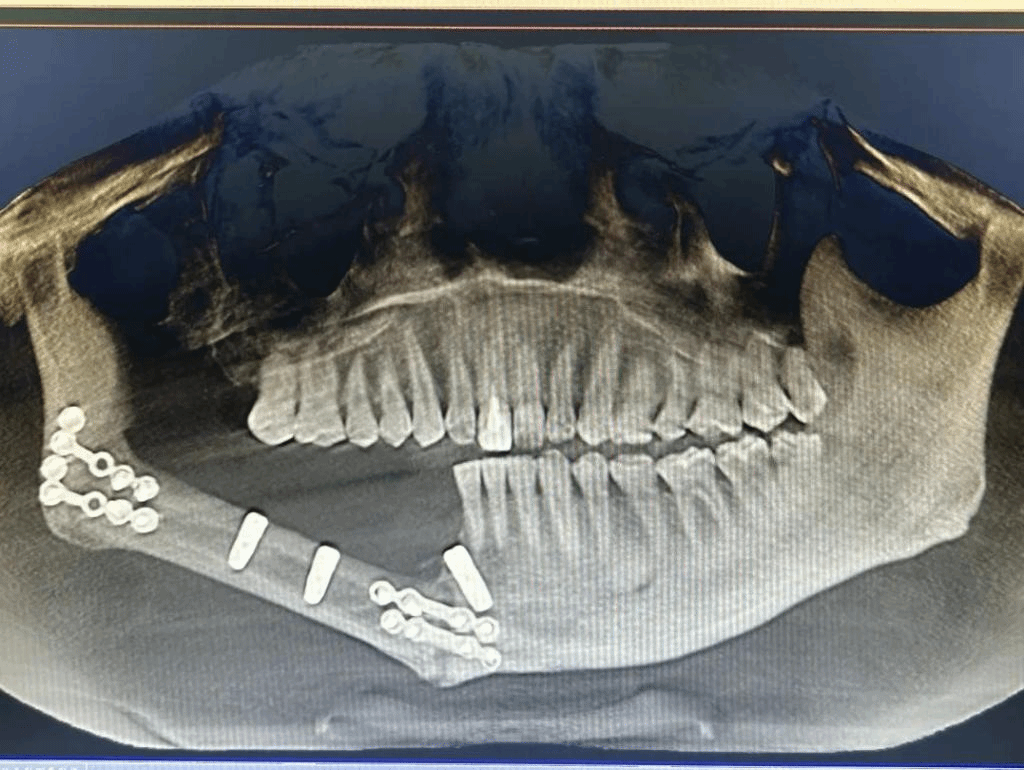

经导航拟定种植方案(左)种植术后影像(右)

相比于传统定位技术,5G数字化动态导航能够更精准的判断最佳种植位置和方向,缩短手术时间,降低安全风险。经过对患者口腔颌面锥形束CT影像的测量,团队确定了手术方案,在5G数字化动态导航下在患者右侧下颌腓骨体突破双皮质层,精确植入3枚种植体,全部初始扭力合格稳固。不到一小时即完成手术,植入位置与导航设计完全一致,术后患者无明显出血、肿胀、疼痛等不良反应,复查种植体在位,无脱落迹象。